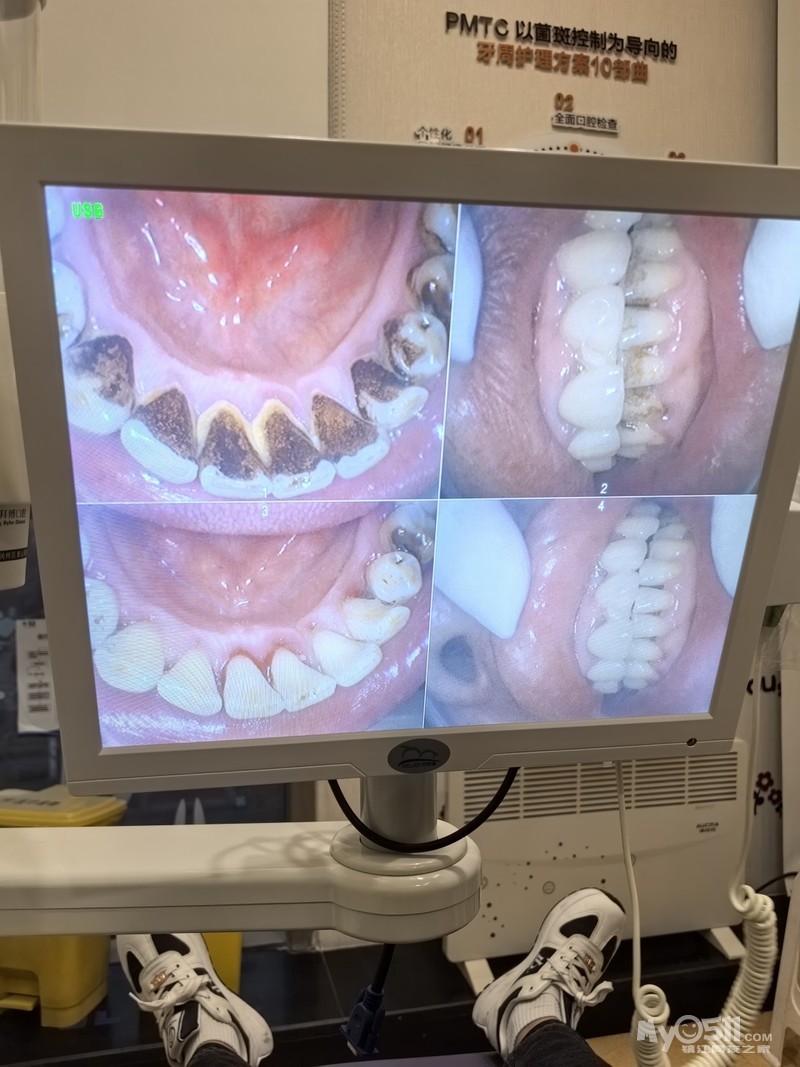

把我爸的大黑牙变白牙

我爸老烟民了,口内牙结石,黑黑的烟渍,今天一起来做个大扫除。带他做了一个PMTC洁牙护理,做完以后回到了白白的牙齿,整个人都看起来清爽年轻了